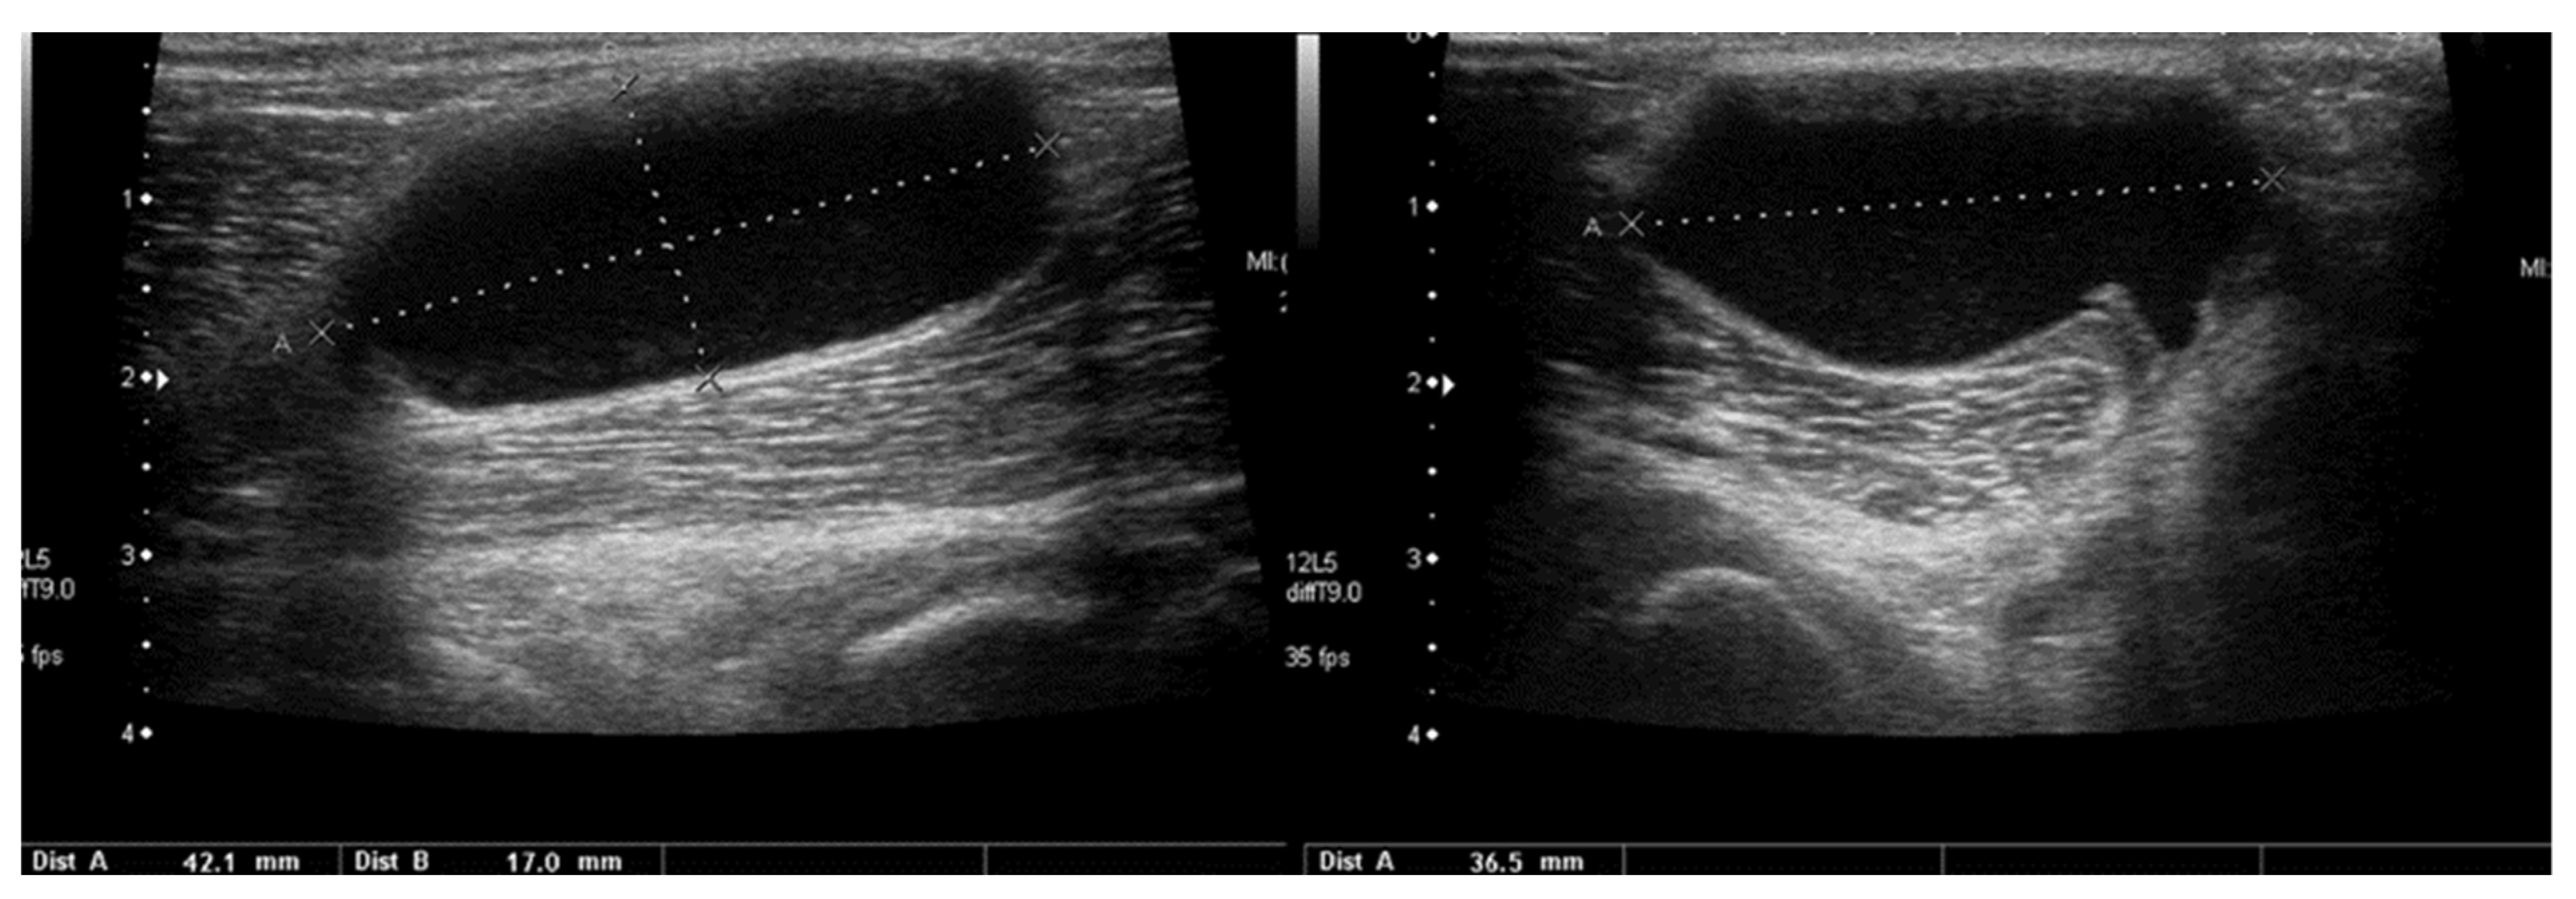

3.2.7. Baker’s Cysts

4. Discussion